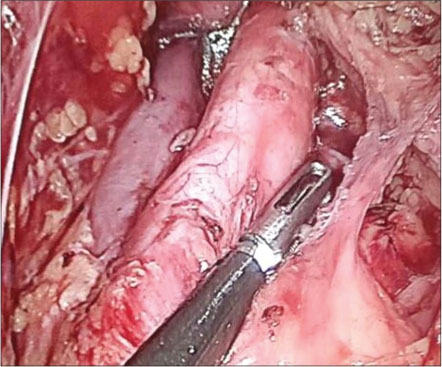

|?Figure. 4? Laparoscopic para-aortic lymphadenectomy

Hence, the diagnosis of high-grade ESS was made with endometrium in proliferative phase and chronic cervicitis with bilateral unremarkable fallopian tubes. The staging of tumor was pT1apNx0 pMx0. Patient and her relatives were informed about the diagnosis, and in consultation with oncologist, radical surgery was planned laparoscopically. Laparoscopic bilateral oophorectomy with pelvic and para-aortic lymph node excision [Figure 4] was done (total 28 lymph nodes were removed) after 4 weeks of primary surgery. The specimen was reported as free of tumor on histopathology. Patient is at present receiving chemoradiotherapy as advised by onco-physician, and till the time of reporting, patients are healthy and under close follow-up.{Figure 4}